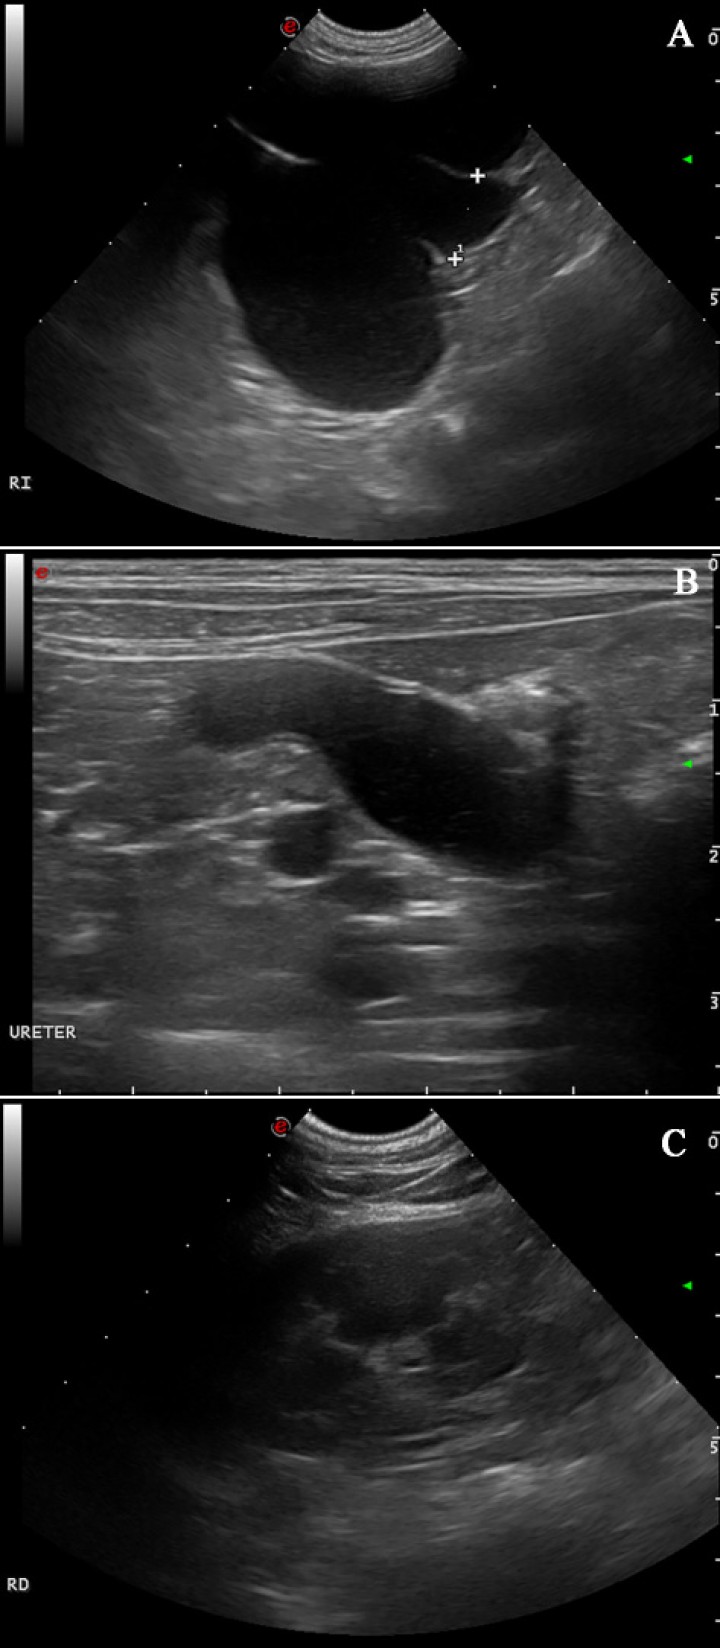

Un año más tarde, la paciente fue remitida para un examen ecográfico porque presentaba polaquiuria y en la analítica sanguínea unos valores de creatinina levemente aumentados (1,53 mg/dl; rango normal: 0,7 a 1,4 mg/dl). El resto de los parámetros se encontraron dentro de los valores de referencia. En la evaluación ecográfica se visualizó una masa de características similares a la observada un año antes y en el mismo lugar (Fig. 1B) de 2,5 cm de diámetro. Además, la pelvis renal y divertículos del riñón izquierdo se encontraban marcadamente dilatados por líquido anecogénico con una mínima remanencia de la corteza renal (Fig. 2A). El uréter ipsilateral también estaba severamente dilatado en todo su trayecto con contenido anecogénico, midiendo 1,65 cm de diámetro y pudiendo seguir su recorrido hasta la masa en la que se encontraba involucrado (Fig. 2B). El riñón derecho presentaba un aspecto normal (Fig. 2C). El diagnóstico presuntivo fue de hidronefrosis e hidrouréter izquierdo severo debido a compresión del uréter izquierdo por parte de un granuloma por cuerpo extraño en el muñón uterino.

Figura 2

Imágenes ecográficas al año de la primera presentación. (A) Hidronefrosis del riñón izquierdo: se observa una marcada dilatación de la pelvis renal y divertículos del riñón izquierdo por líquido anecogénico con una mínima remanencia de la corteza renal. (B) Severo hidrouréter izquierdo con contenido líquido anecogénico. (C) Riñón derecho de aspecto normal.